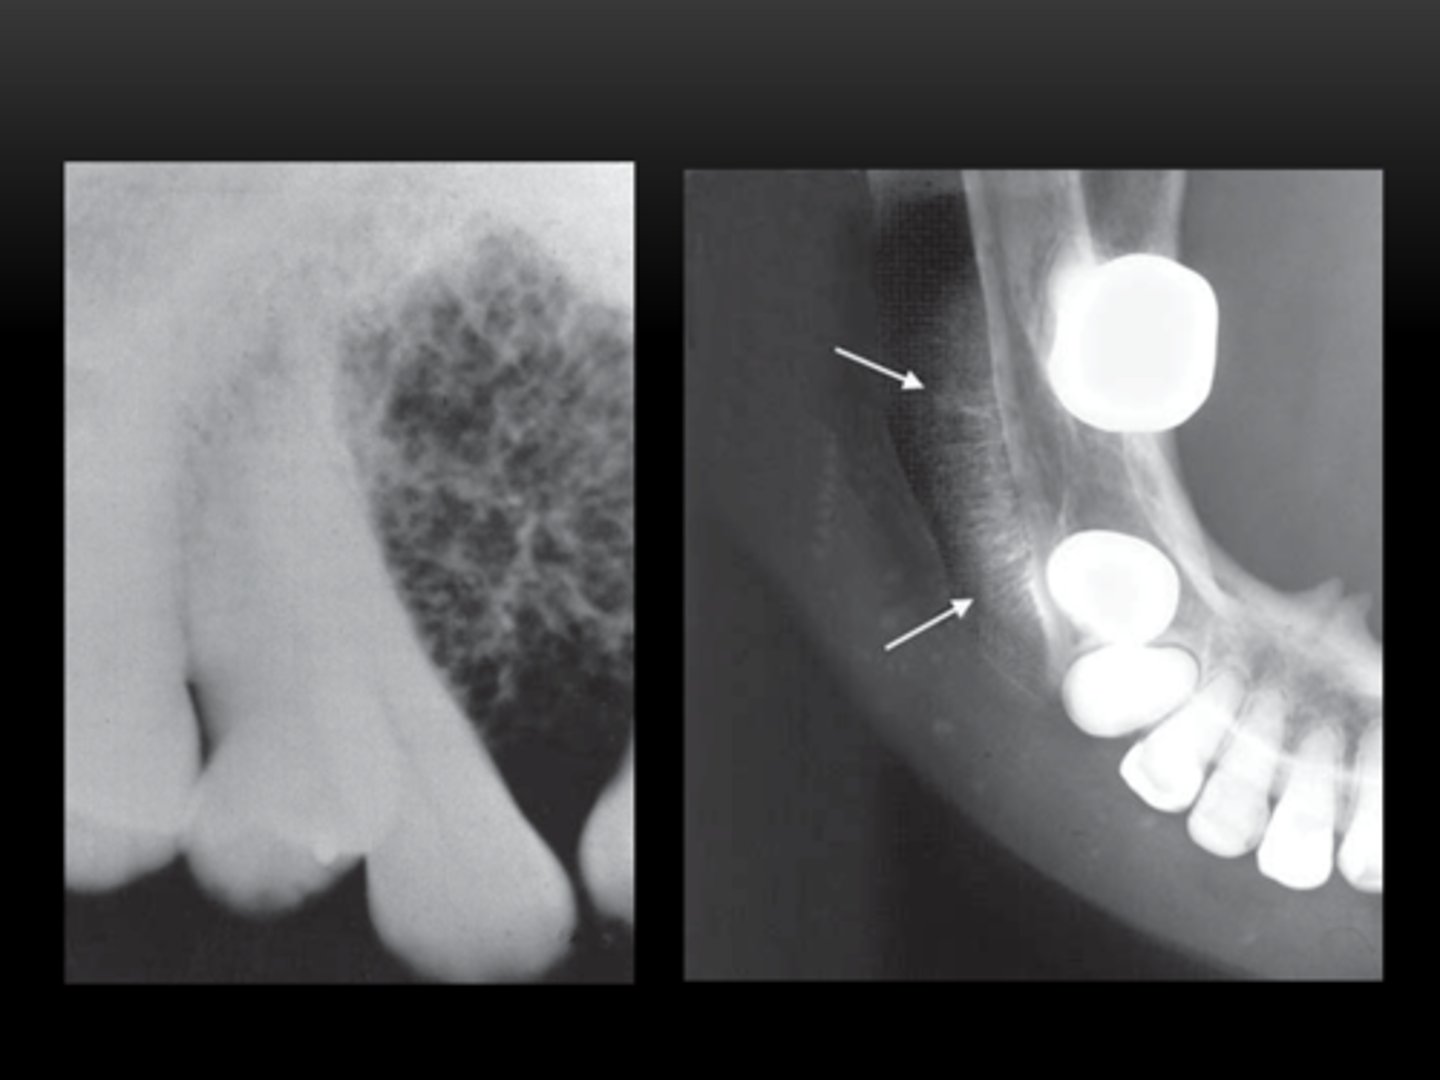

Osteosarcoma Radiographic Signs

radiographic (widened PDL)

Mixed (fleck, sunray appearance)

ill-defined margins

irregular

cortical destruction

root resorption (displacement)